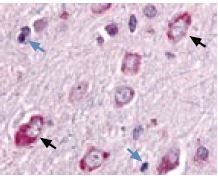

Immunohistochemical staining of HCN1 with Anti-HCN1 antibody (#APC-056) in in rat basal ganglia. Picture showing the putamen nucleus. Neuronal cells (black arrows) were strongly stained, whereas glial cells (blue arrows) show no staining at all. Color reaction is red and counterstain is hematoxylin.